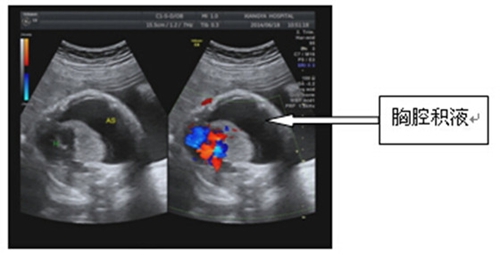

经B超下测量该胎儿胸腔内聚集了约250毫升的粘状胸水,强大的压力将胎儿的肺组织压缩得很小,肺泡不能发育,并将心脏顶到一侧,胎儿危在旦夕。

在明确了疾病的危害后,最好的治疗方法就是立即将胸水抽出,让压缩的肺松解、肺泡扩张发育、心脏回复正常位置。6月25日和27日,姚若进教授带领翦羽主治医师对患病胎儿先后两次进行了“B超引导下经子宫腔羊膜腔胎儿胸腔穿刺术”,用一根长约15厘米的穿刺针,由陈女士的腹部进入子宫并经过羊膜腔,在B超指引下看准时机一针插入胎儿的胸腔,用注射器将积液慢慢抽出。

经过两次胸腔穿刺后,胎儿右侧胸腔只剩下少量的积液,而肺部也已明显膨胀扩张,获得了解放的心脏位置正常且因此跳得越发强劲。